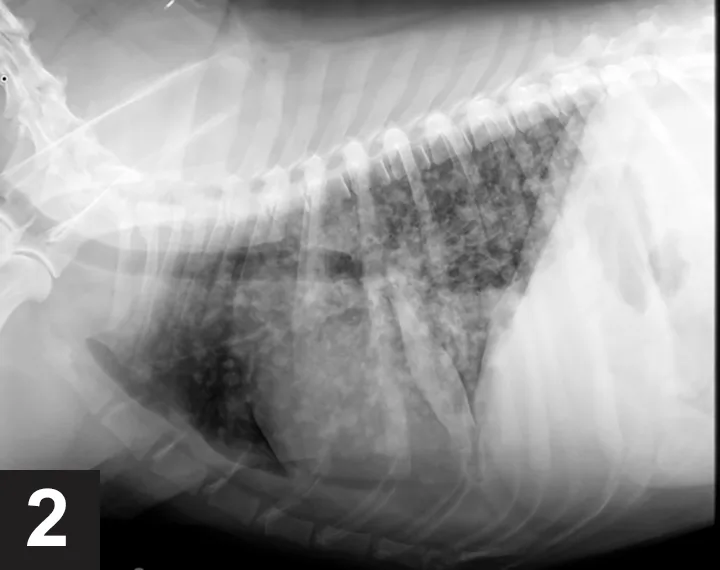

The owner consented to further testing, and a radiographic pattern consistent with pulmonary blastomycosis was identified on thoracic radiographs (Figure 2). Ocular examination was unremarkable. Mild leukocytosis and monocytosis were evident on CBC, while the serum chemistry panel was unremarkable. A urine sample was submitted for Blastomyces dermatitidis enzyme immunoassay (EIA) for additional confirmation, and treatment with itraconazole was started.

FIGURE 2

Thoracic radiograph of a dog with blastomycosis. Note the nodular interstitial pattern with patchy alveolar infiltrates. Image courtesy Dr. Shawn MacKenzie